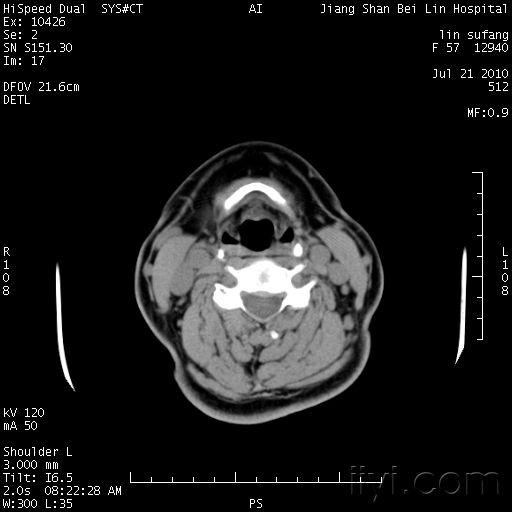

60岁/女,体检发现甲状腺结节.增强血管样强化,您见过没---(有结果)

图片尺寸512x512